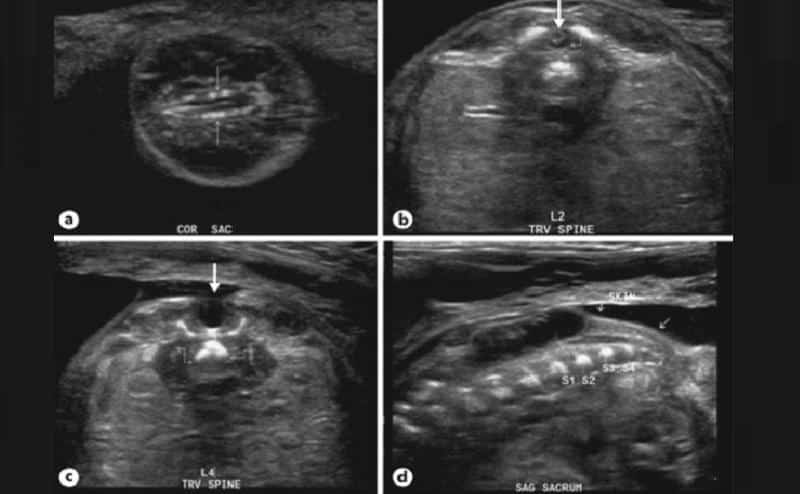

Как правило, наличие недуга выявляется во время ультразвукового исследования. Необходимо провести генетические тесты и взять образцы жидкости из матки. Это помогает оценить вероятность возникновения деформаций. Такой подход позволяет организовать более безопасные роды, минимизируя риск повреждений и инфекций.

У новорожденных можно выявить только тяжелые формы заболевания. О необходимости дополнительных исследований может свидетельствовать наличие пятна на спине или пониженный мышечный тонус.

Часто спина бифида позвоночника обнаруживается на рентгеновских снимках во время плановых медицинских осмотров.